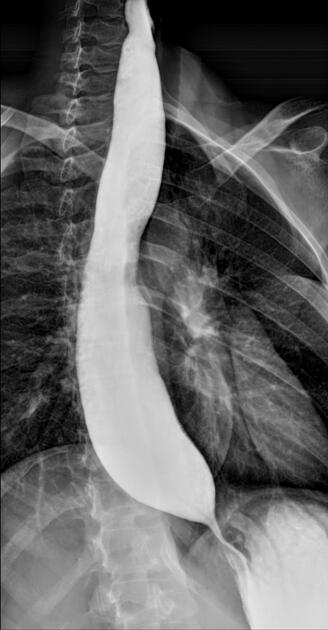

A 37-year-old man presents to the physician because of dysphagia and regurgitation for the past 5 years. In recent weeks, it has become very difficult for him to ingest solid or liquid food. He has lost 3 kg (6 lb) during this time. He was admitted to the hospital last year because of pneumonia. Three years ago, he had an endoscopic procedure which partially improved his dysphagia. He takes amlodipine and nitroglycerine before meals. His vital signs are within normal limits. BMI is 19 kg/m2. Physical examination shows no abnormalities. A barium swallow X-ray is shown. Which of the following patterns of esophageal involvement is the most likely cause of this patient’s condition?